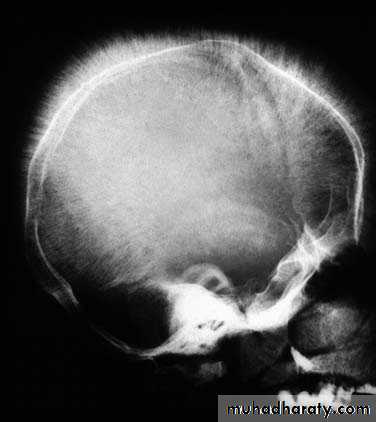

• Widened intratrabecular spaces, hair-on-end appearance of skull radiographs

hair-on-end appearance of skull